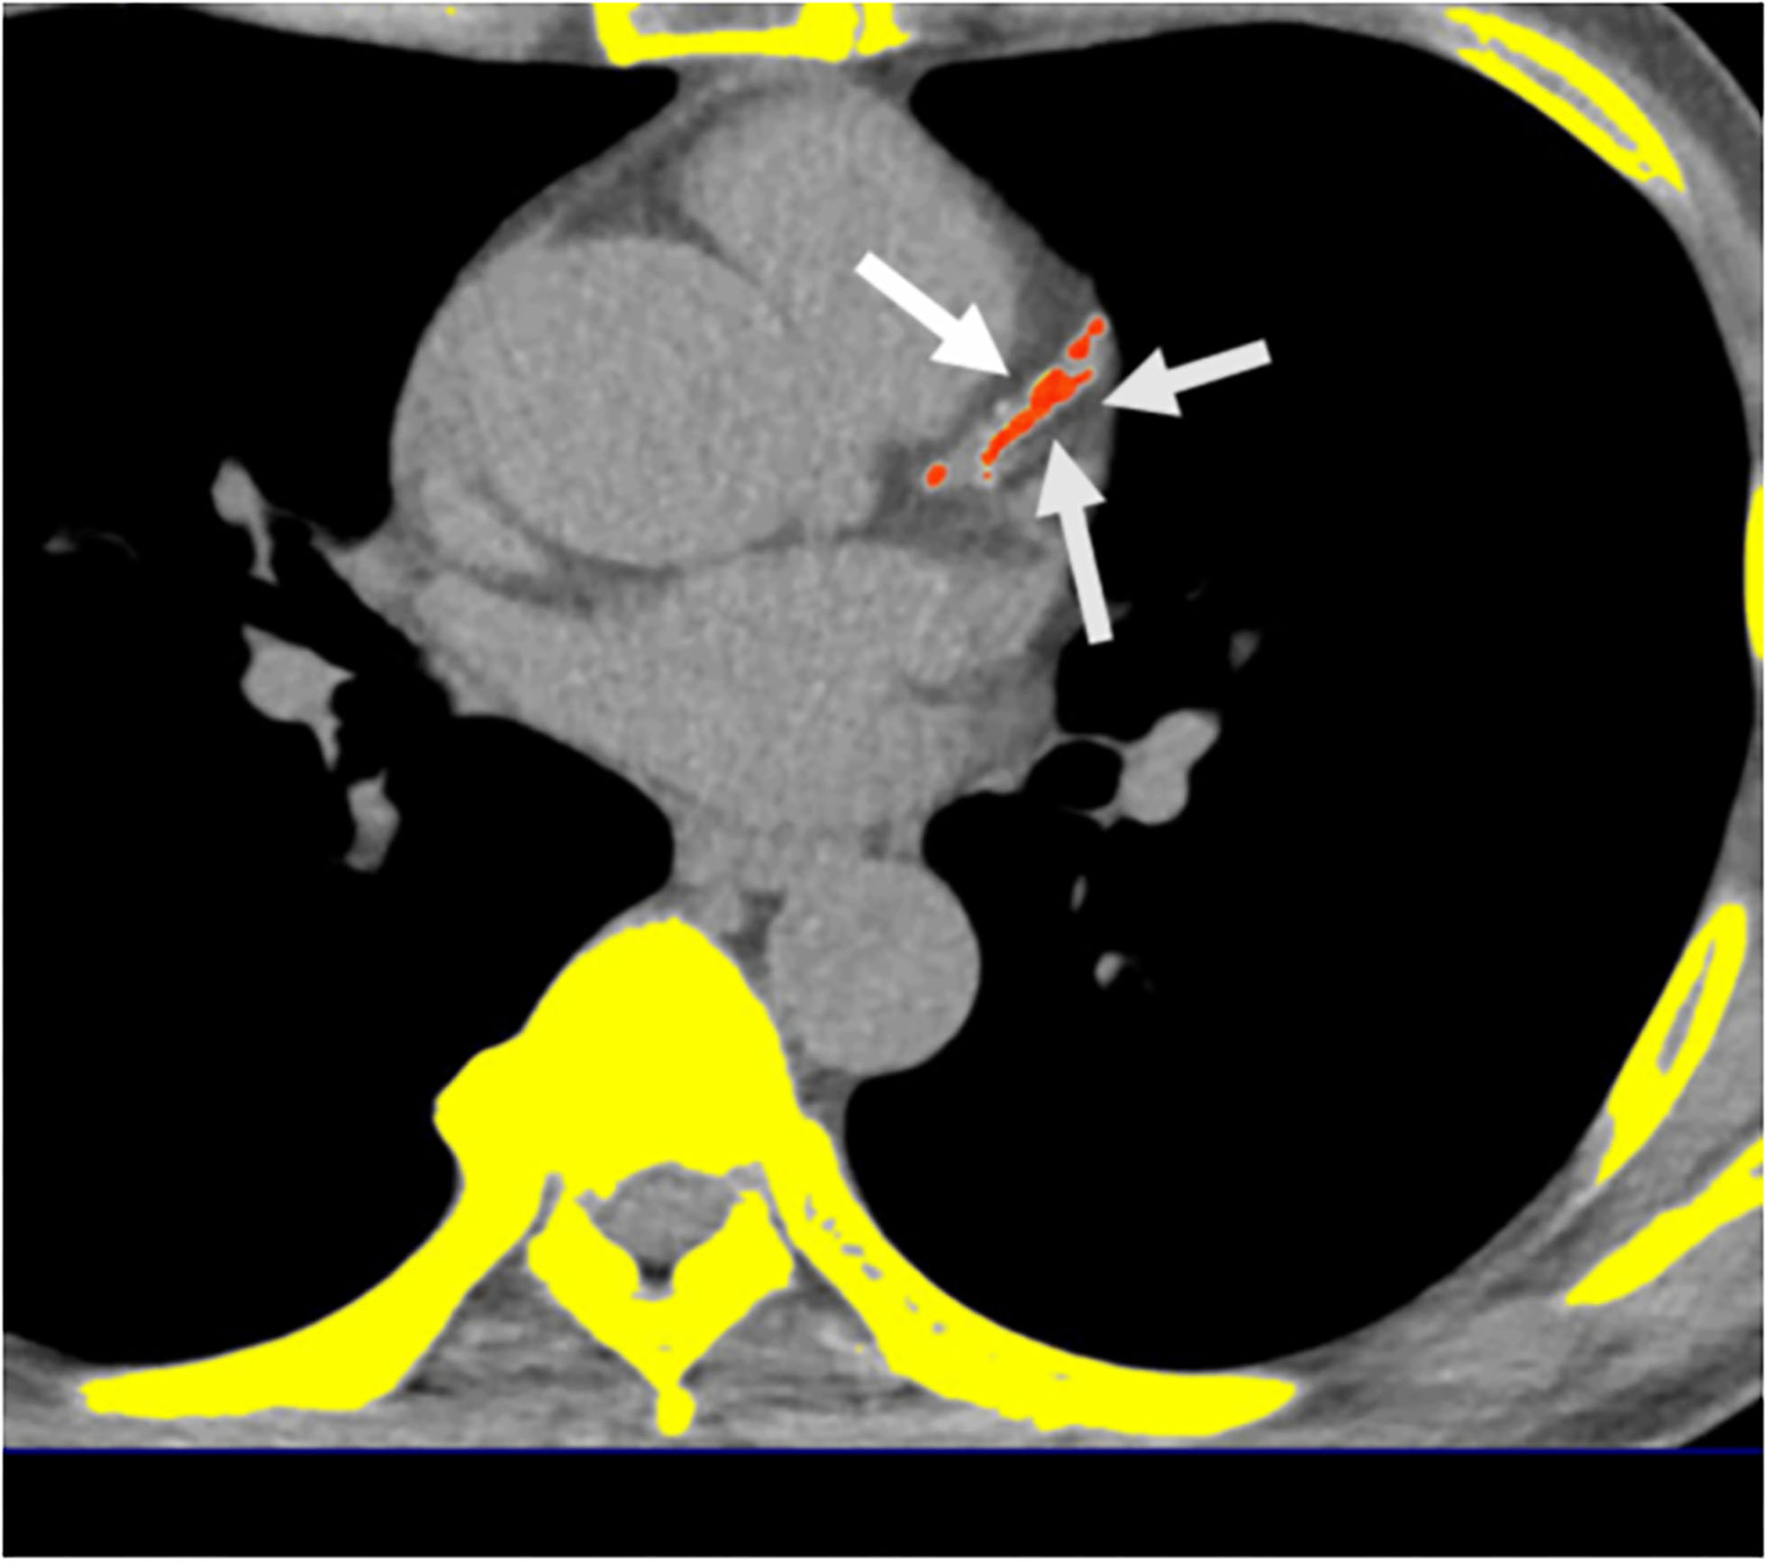

A 16-slice MDCT scanner (Sensation 16; Siemens Medical Solutions, Forchheim, Germany) with 16- ×0.75-mm collimation, rotation time of 420 ms, and tube voltage of 120 kV was used to measure the calcification of all coronary arteries using a dedicated offline workstation (Aquarius 3D Workstation; TeraRecon, San Mateo, CA, USA). A site with a density >130 HU and lasting at least six pixels were defined as a “coronary calcified lesion.” Distinct atherosclerosis that was clinically important was defined by the presence of CAC; the burden of atherosclerosis that was defined by CAC score (CACS) which was semi-quantitatively measured using the Agatston score by multiplying every lesion (area) by a weighted CT attenuation score of the lesion (Figure 2) (32).

Figure 2

Multidetector computed tomography (MDCT) demonstrated the quantification of CACS. Semi-automatic quantification of CACS burden using Agatston scoring. *Orange color regions indicate visceral fat tissue. White arrows indicate coronary calcification lesions.